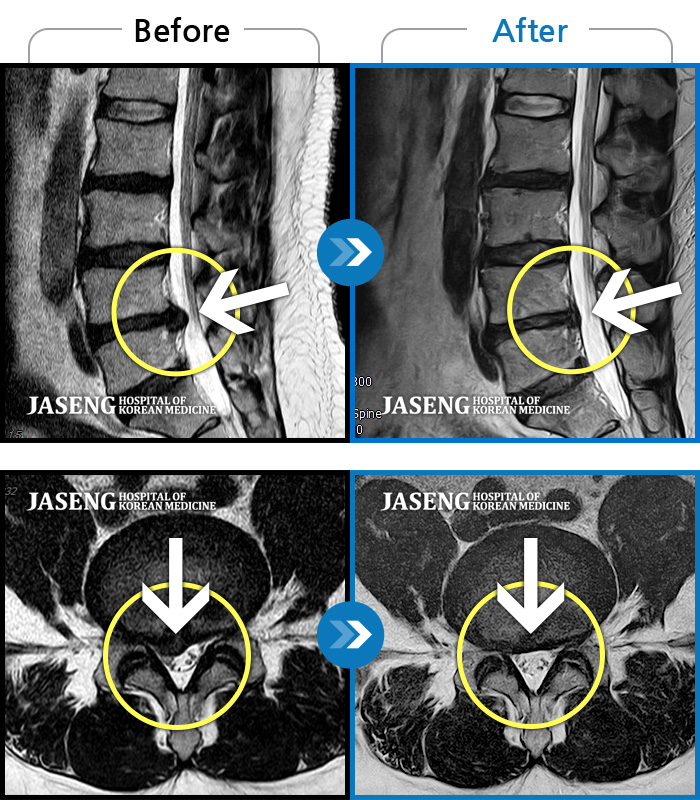

허리디스크

강남 · 강만호 원장

허리 통증 및 왼쪽 다리 근력저하 감각저하로 일상생활이 불가능했습니다.

촬영시기

2024.05.18 ~ 2025.12.03

2025.12.19